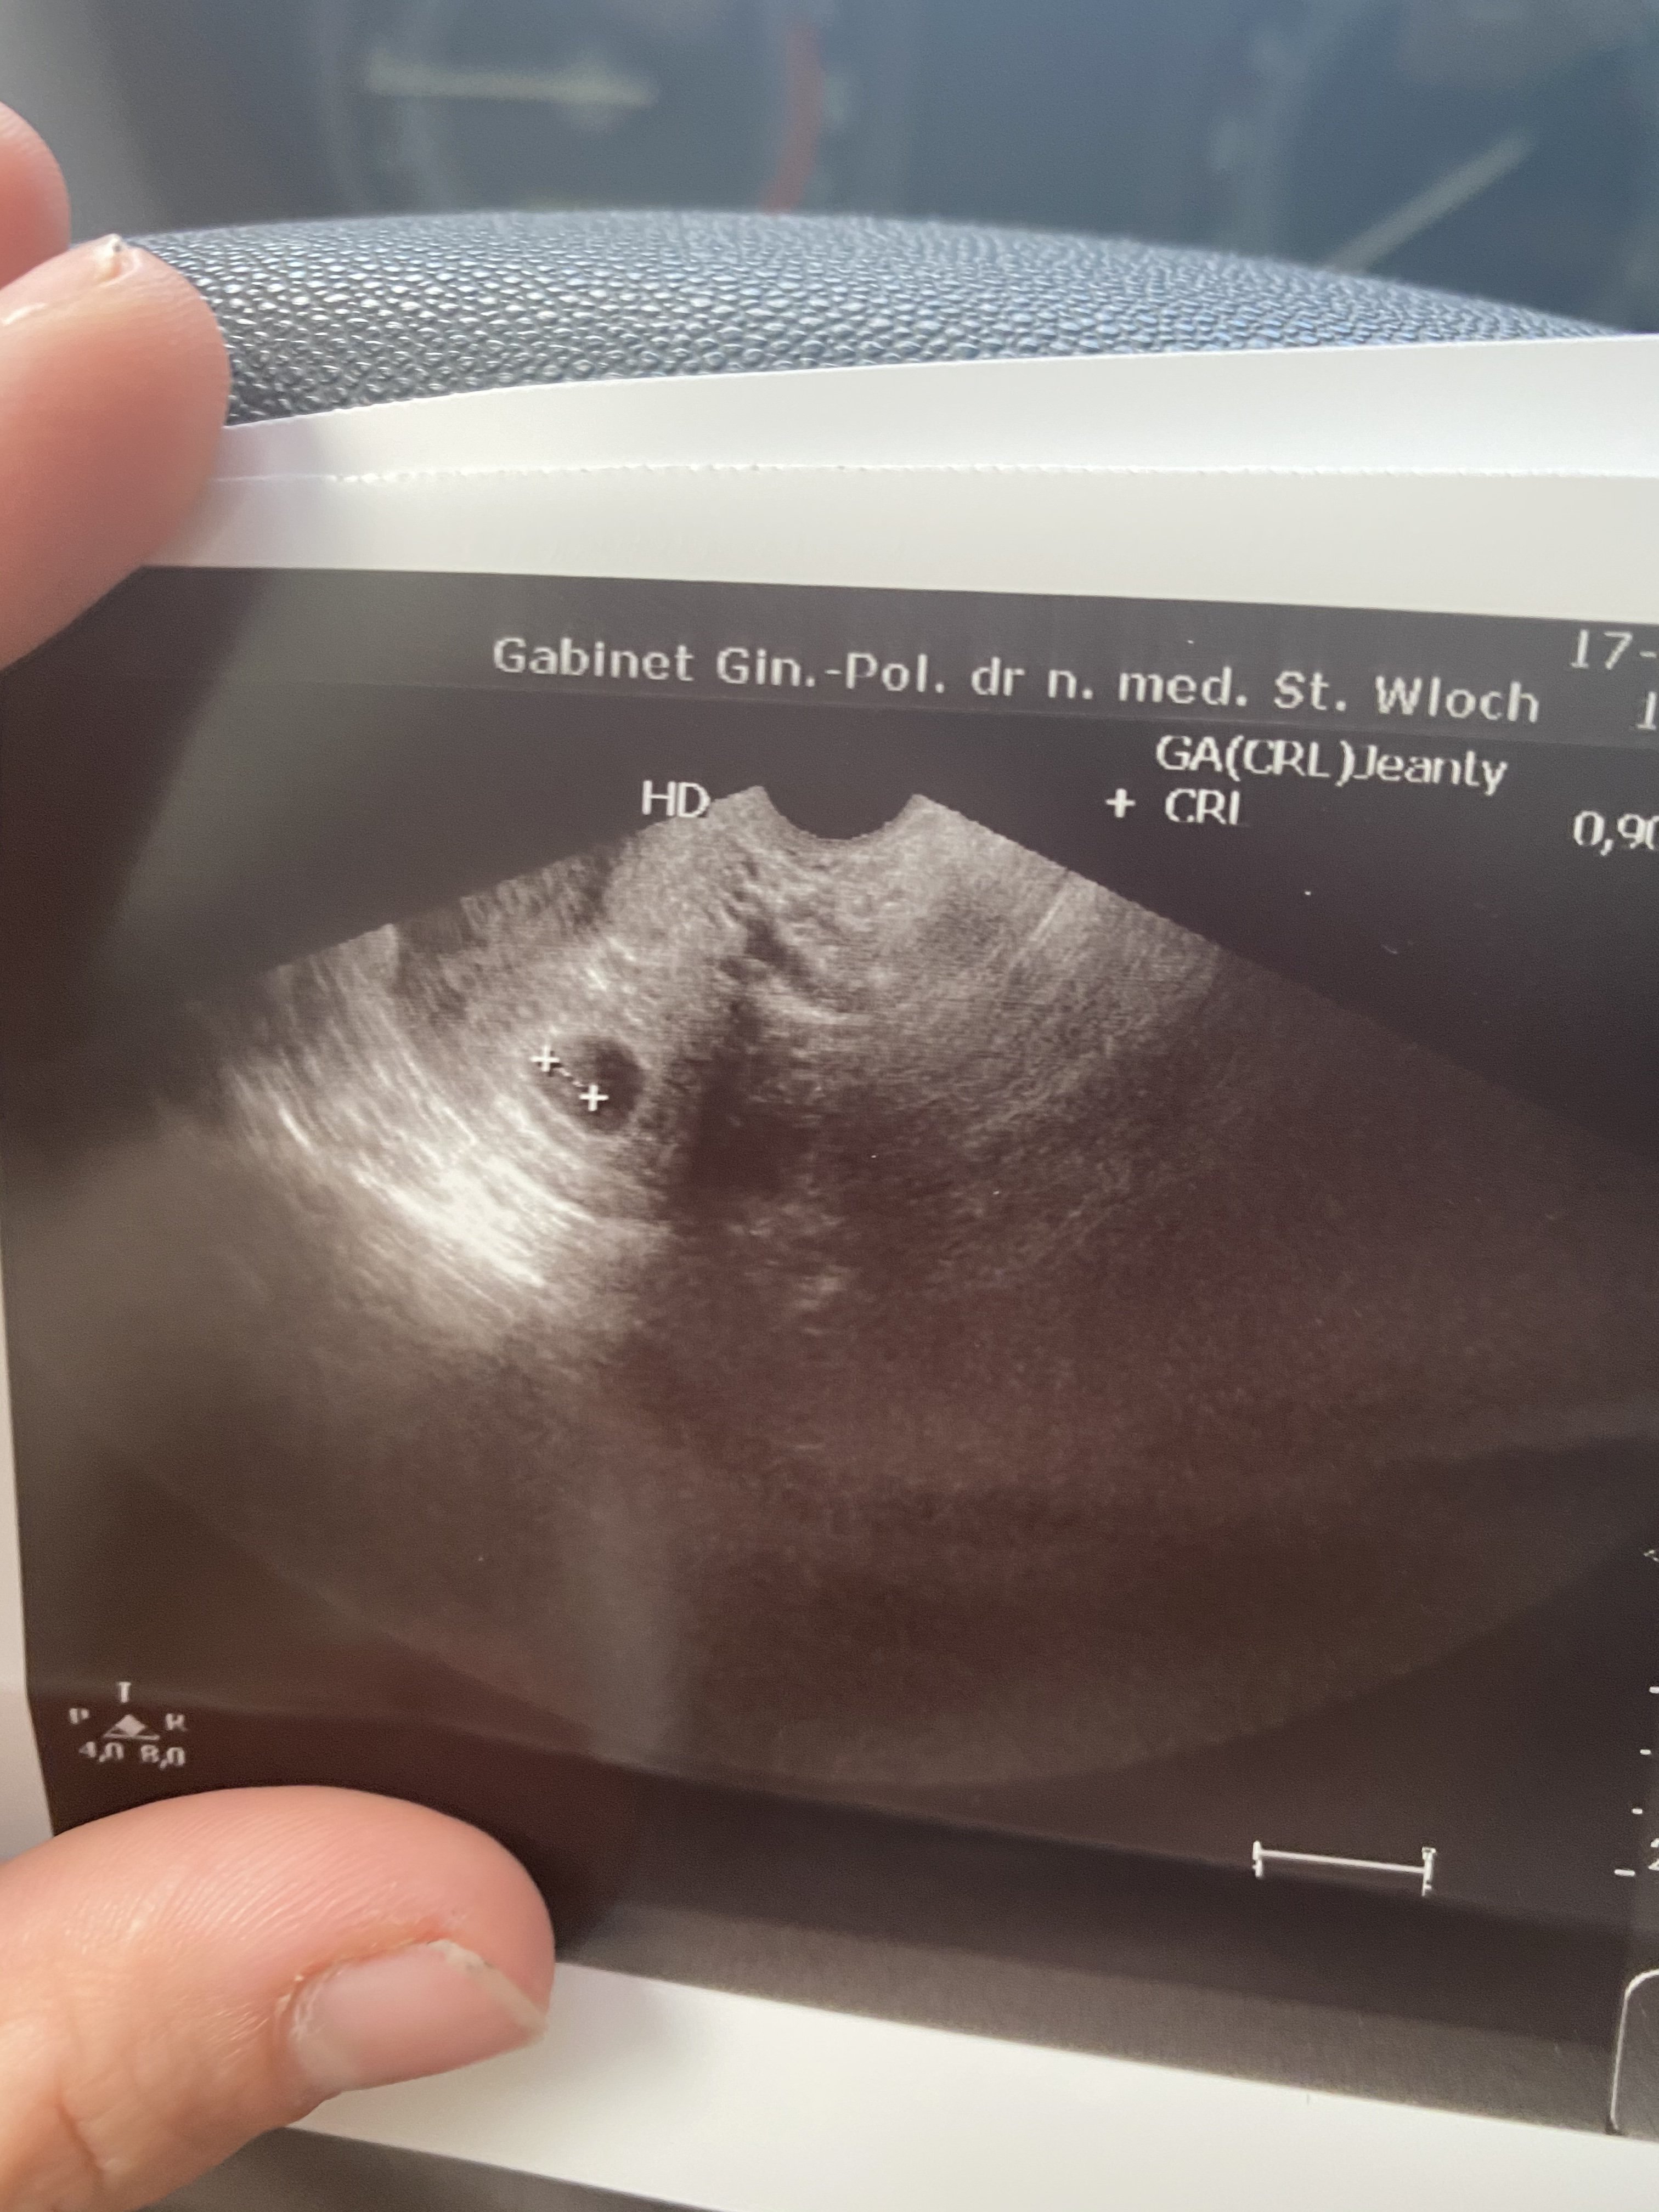

O takie wieści mi chodziło, dziękujęKochana obecnie jestem w 14tc. Tutaj zarodek miał 0,9 Crl i wychodził 6t5d i również lekarz powiedział ze jeszcze nie ma tętna. Za tydzień już biło serduszko. Trzymam kciuki![]()

Ja po tej wizycie przeszukałam cały internet ,bo tez myślałam ze to juz za późno żeby serduszko zabiło. Nawet przychodząc na następna wizytę mówię do lekarza ,ze ja nie mam nadziei ze jest wszystko dobrze,ze objawów nawet już nie mam a tam zarodek i bijące serduszkoO takie wieści mi chodziło, dziękujębardzo bym chciała żeby i u mnie tak było. Nie jestem panikara, nie załamuje się ale chciałabym odzyskać trochę nadziei bo ciężko się z tym pogodzić ze to juz drugie nie powodzenie pod rząd

WspanialeJa po tej wizycie przeszukałam cały internet ,bo tez myślałam ze to juz za późno żeby serduszko zabiło. Nawet przychodząc na następna wizytę mówię do lekarza ,ze ja nie mam nadziei ze jest wszystko dobrze,ze objawów nawet już nie mam a tam zarodek i bijące serduszko❤ A beta dzień wcześniej prawie 20tysiecyZobacz załącznik 1197605